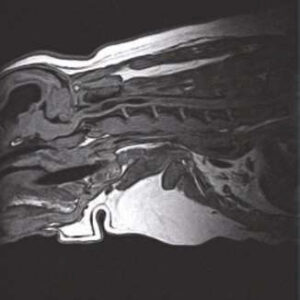

The PANION PRO comes with the double-pole open magnet design with a wide opening gap of 40 cm to accommodate large-sized animals on an efficient patient handling platform, the strongest gradient amplitude at 33mT/m and slew rate of 90 T/m/s, among all other open MRI systems, resulting in high spatial resolution of images in short scan time. The 6-direction patient table permits iso-centre imaging of all anatomical regions.

Clinical Images